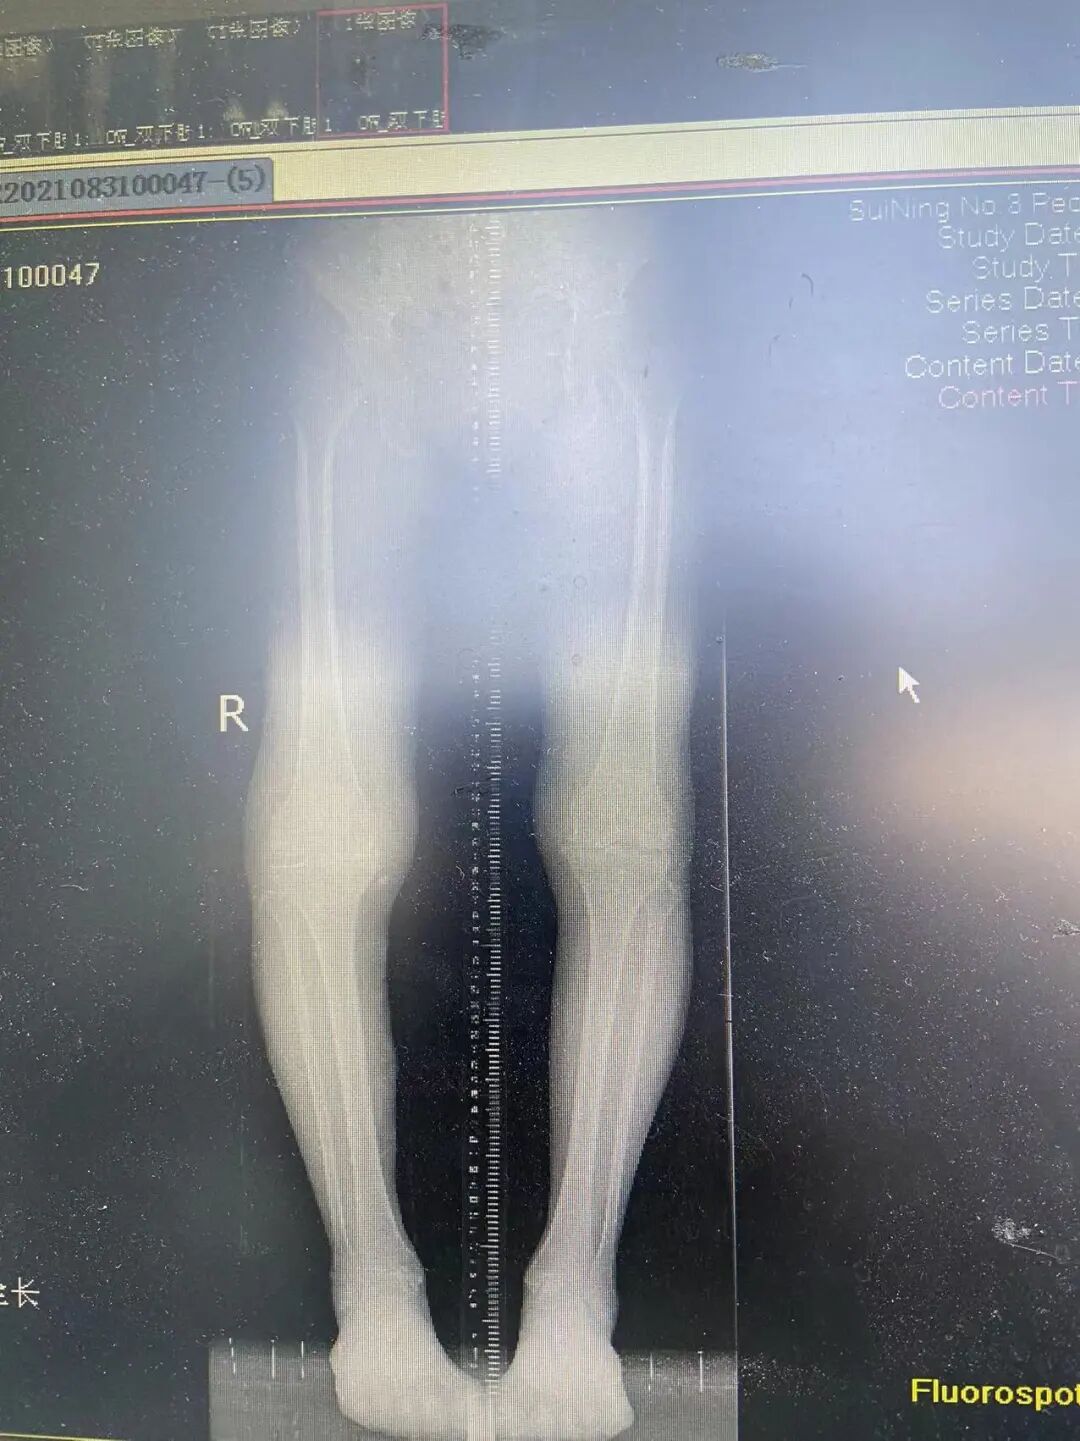

右膝重度骨关节炎

右膝全膝置换术